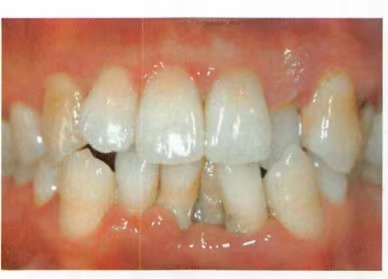

牙齒位置異常擁擠 錯牙合畸形

牙齦出血的炎癥和出血,牙齦呈現(xiàn)暗紅色或鮮紅色,牙齦腫脹,質(zhì)地松軟

;